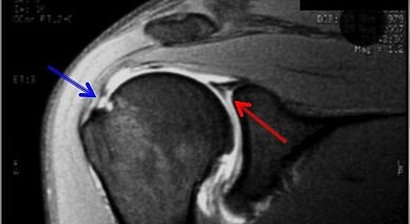

Rotatorenmanschettenruptur

Als Rotatorenmanschette wird jene Muskelgruppe bezeichnet, welche sich zwischen dem Schulterblatt (Scapula) und dem Oberarmkopf (Caput humeri) erstreckt und wie eine Muskelhaube den Großteil des Oberarmkopfes umschließt. Eine intakte Rotatorenmanschette gewährleistet durch das funkt...